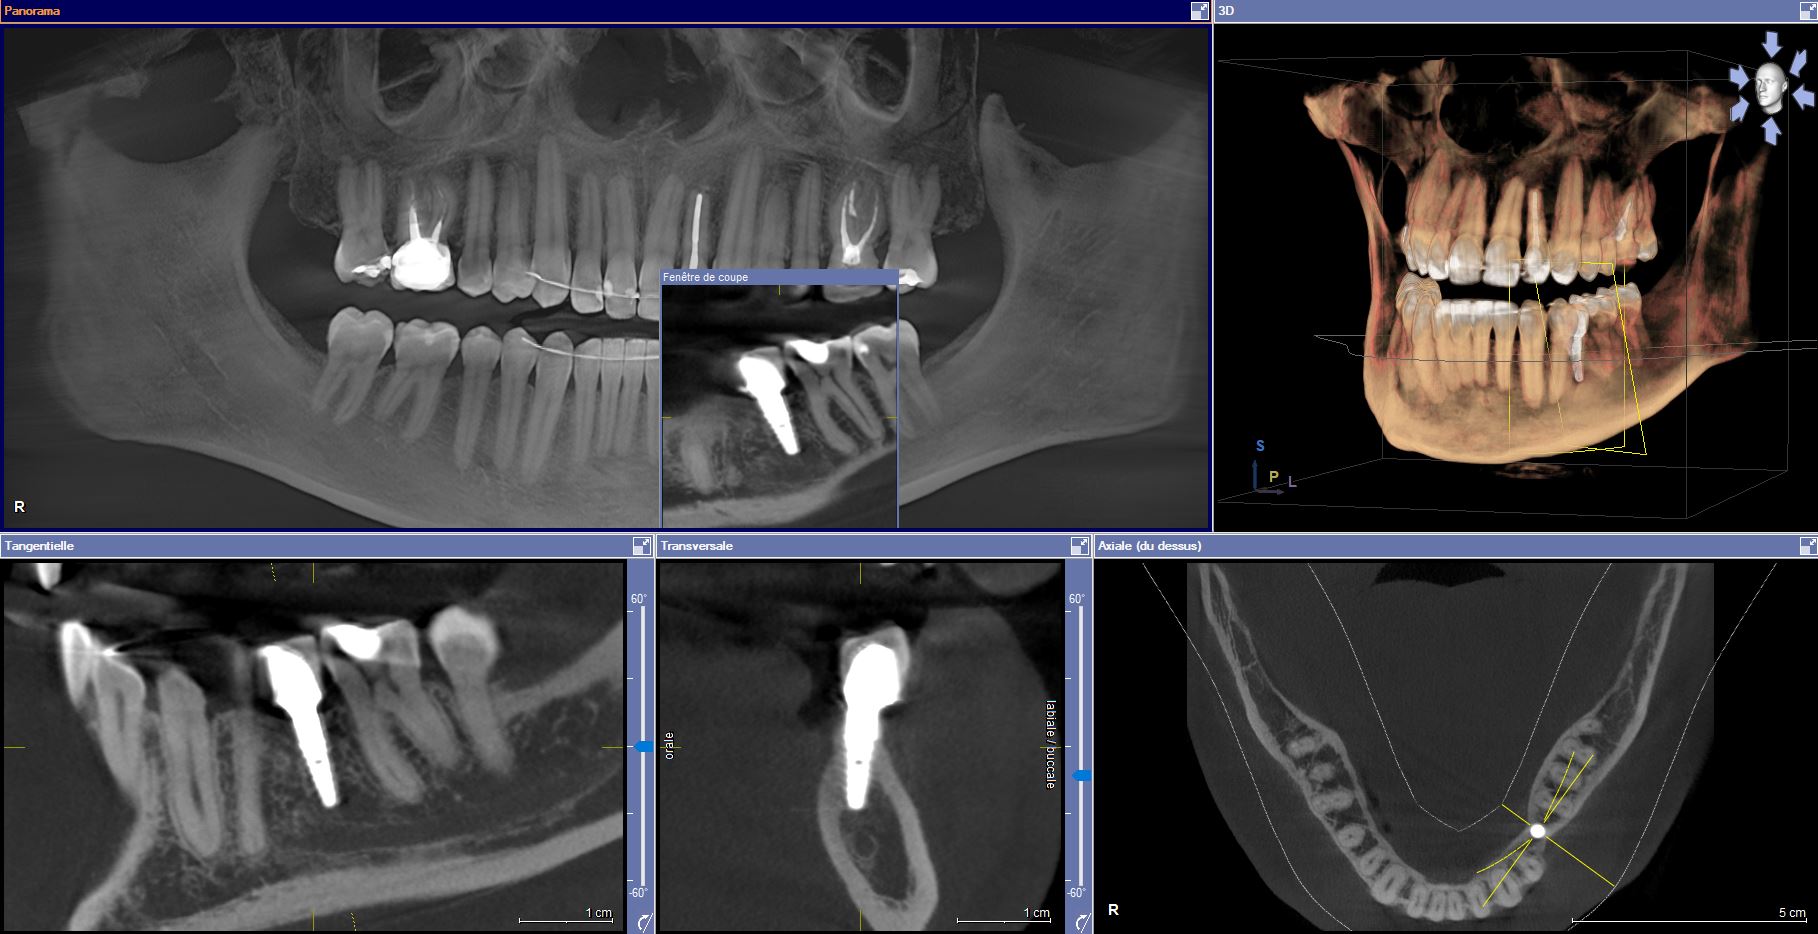

Nous disposons également de l’option 3D Cône Beam équivalent en qualité à un scanner mais beaucoup moins irradiant. Ces images permettent de nombreuses explorations

• Recherche de foyers infectieux ou kystes

• Recherche de canaux atypiques pour les traitements endodontiques (dévitalisation)

• Visualisation des impératifs anatomiques pour les dents de sagesses

• Planification de la position des implants dentaires

Le Cone Beam est considéré comme ayant été un progrès important pour l’imagerie médicaleUtilisant un faisceau conique de rayons X, il permet un examen performant des tissus minéralisés , mettant en évidence avec une excellente précision des lésions osseuses, fractures, infections, kystes et corps étrangers. En dentisterie, il permet la planification du positionnement des implants afin d’éviter les obstacles anatomiques.